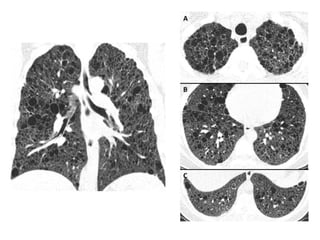

A, Unenhanced axial high-resolution CT through left mid (A) and lower (B) lung

show peripheral honeycombing, which is greatest in lower lobe,

accompanied by traction bronchiectasis and scattered peripheral reticular

opacities. Honeycombing is most prominent feature in this patient, typical for

idiopathic pulmonary fibrosis